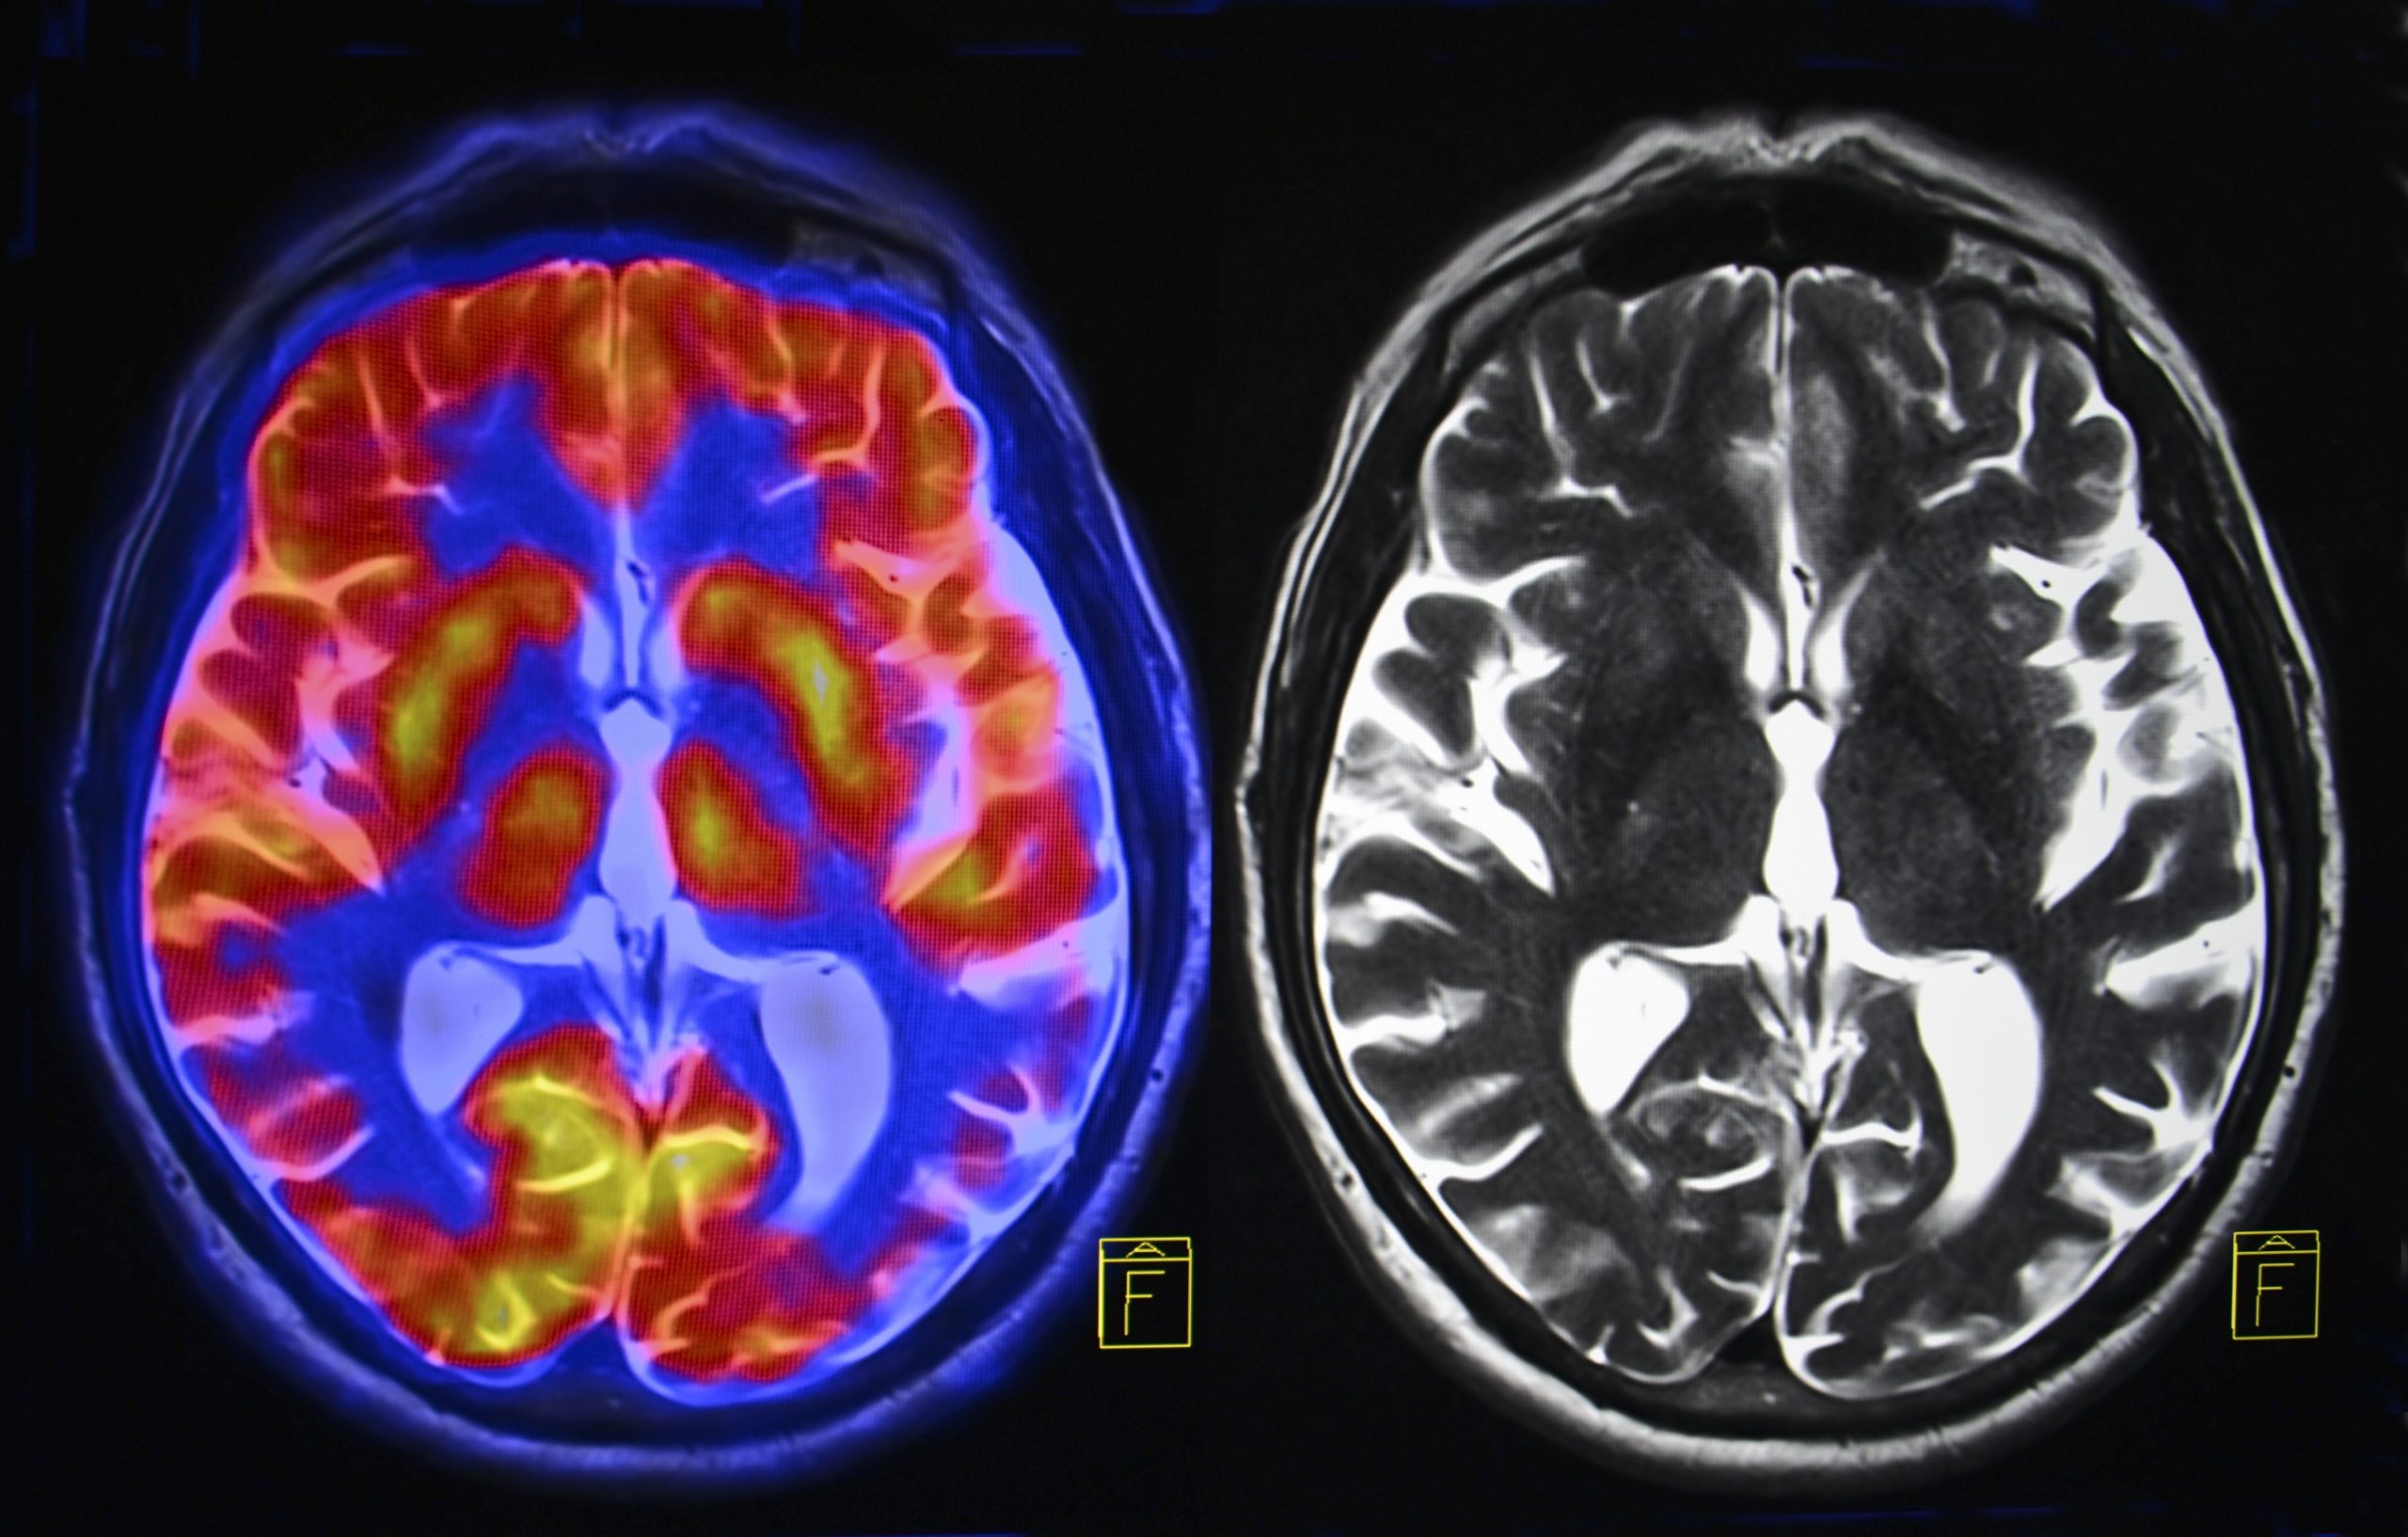

Медицинская диагностика: КТ и МРТ головного мозга